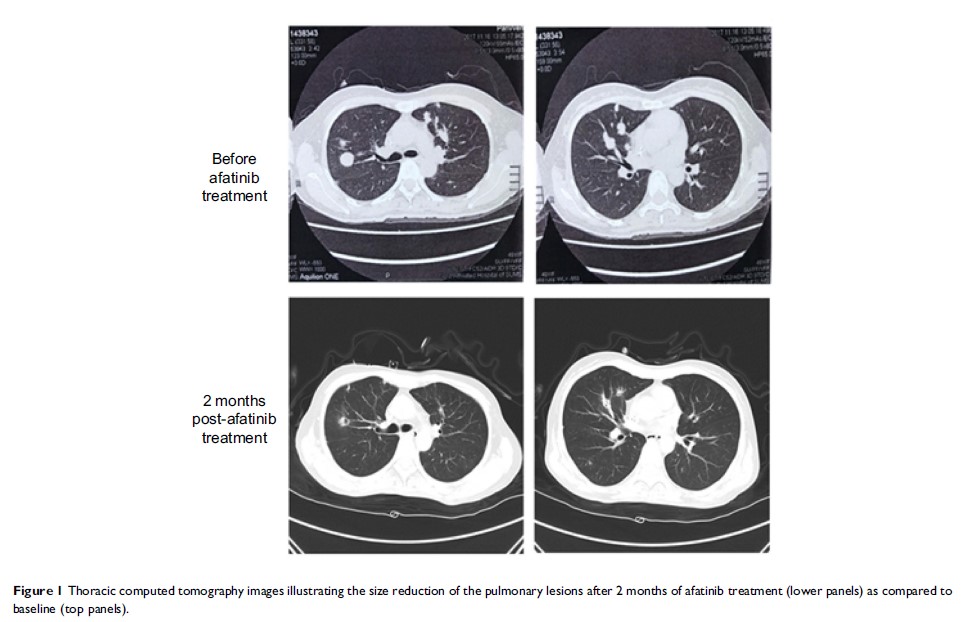

阿法替尼在 HER2 扩增阳性子宫内膜样腺癌患者中的疗效:一份病例报告